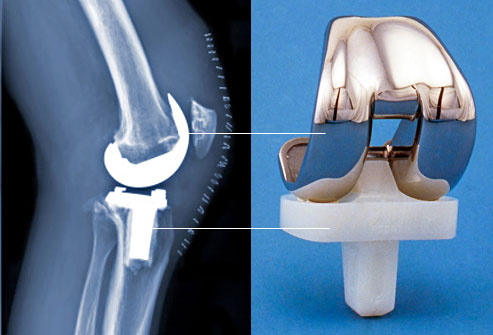

Total knee replacement is a relatively common, safe and good option for chronic osteoarthritis knee . Osteoarthritis (OA) is the most common joint disease, affecting an estimated more than 240 million people worldwide, including an estimated more than 32 million in the US. Osteoarthritis is the most frequent reason for activity limitation in adults.